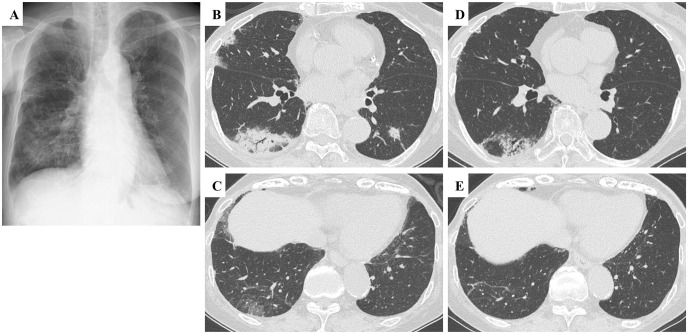

Abemaciclib, a cyclin-dependent kinase 4/6 inhibitor, is crucial in treating hormone receptor-positive, human epidermal growth factor receptor 2-negative metastatic or recurrent breast cancer. However, its association with drug-induced interstitial lung disease (DI-ILD) is concerning. We present an 82-year-old woman with breast cancer receiving abemaciclib, who developed persistent cough and malaise. Initial diagnostics suggested pneumonia, supported by ground-glass opacities and consolidations on chest high-resolution computed tomography. Suspecting DI-ILD, a transbronchial lung cryobiopsy (TBLC) was performed, revealing fibrosing organizing pneumonia and confirming abemaciclib-induced ILD. Discontinuing abemaciclib led to significant symptom improvement, supporting the diagnosis. This case report describes the clinical presentation and diagnostic approach in a patient with suspected abemaciclib-induced ILD, including the use. To our knowledge, this is the first reported case of fibrosing organizing pneumonia as a histopathological pattern in abemaciclib-induced ILD, expanding knowledge of this therapy's pulmonary adverse events. Histopathological features included diffuse lymphocytic infiltration, polypoid intra-alveolar fibrosis, intraluminal granulation tissue plugs with dense hyalinization, hyalinized fibrotic alveolar septa lesions, and obliterative fibrotic processes affecting alveolar ducts. Our case suggests that TBLC might be useful in recognizing DI-ILD by providing detailed lung tissue examination, which can facilitate early diagnosis and guide management. Identifying fibrosing organizing pneumonia indicated a potentially corticosteroid-responsive pathology, suggesting a more favorable prognosis compared with patterns like diffuse alveolar damage. This case highlights the potential for abemaciclib-induced ILD to occur even after prolonged treatment periods, emphasizing the importance of vigilance and consideration of diagnostic intervention for patients on cyclin-dependent kinase 4/6 inhibitors presenting with respiratory symptoms. Timely recognition and appropriate management may mitigate adverse outcomes. Further studies are needed to confirm these findings and to better understand the role of TBLC and histopathological examination in diagnosing and managing abemaciclib-induced ILD.